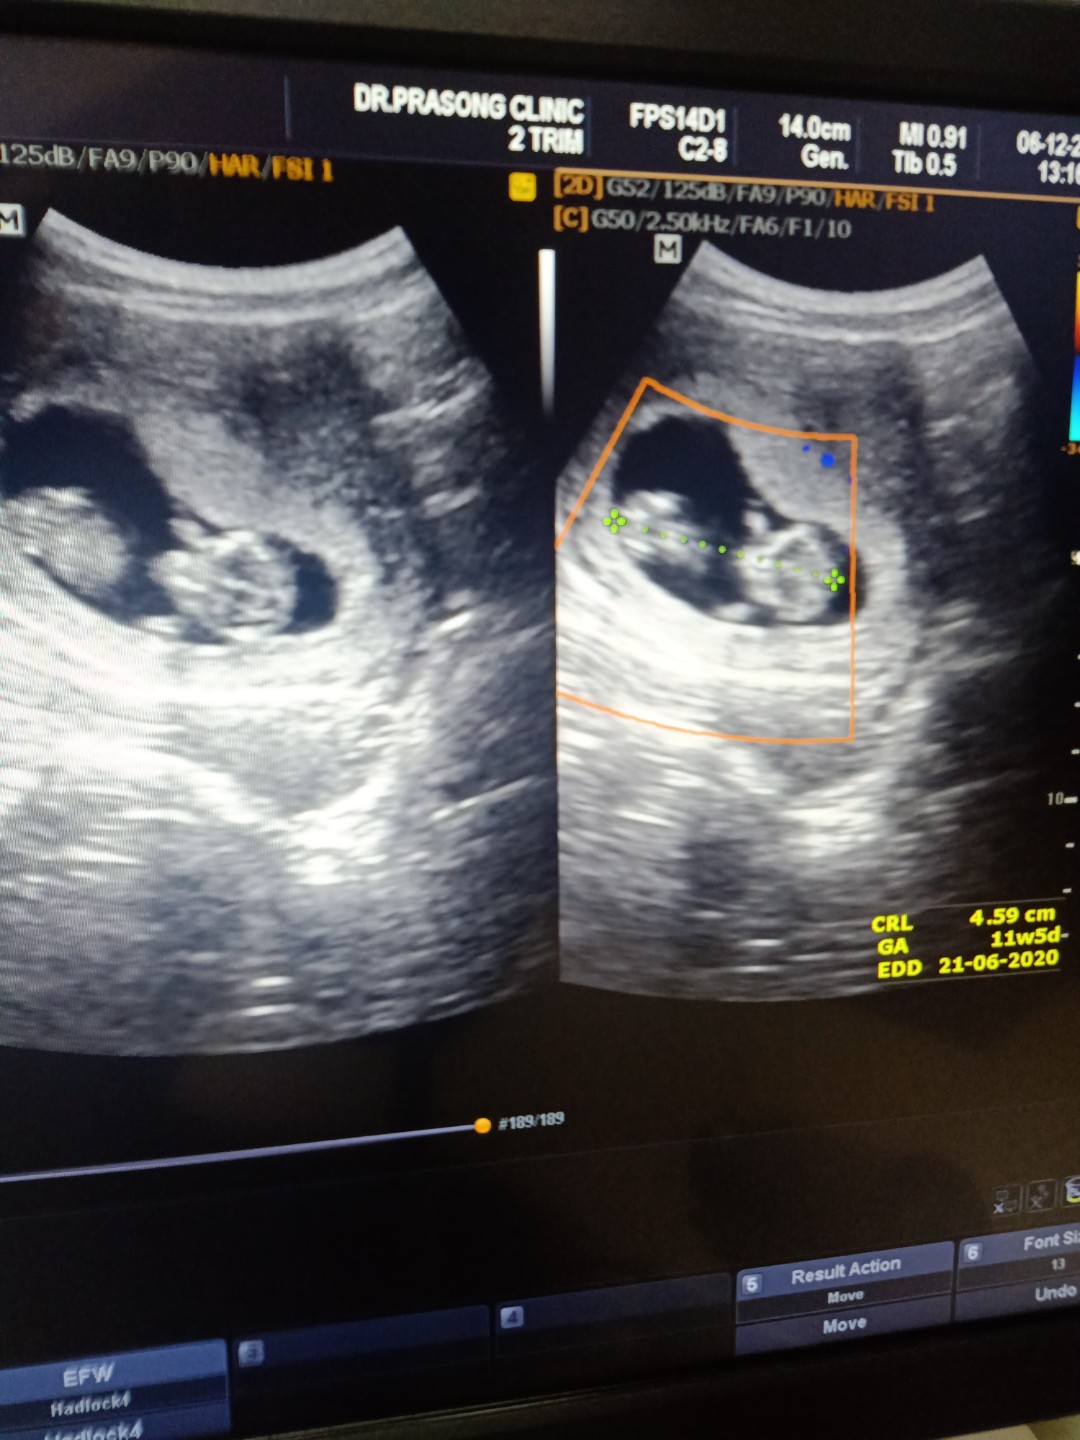

ไปซาวมาเมื่อวาน 10w4d

ตอนนั้น10+6วีคค่ะ